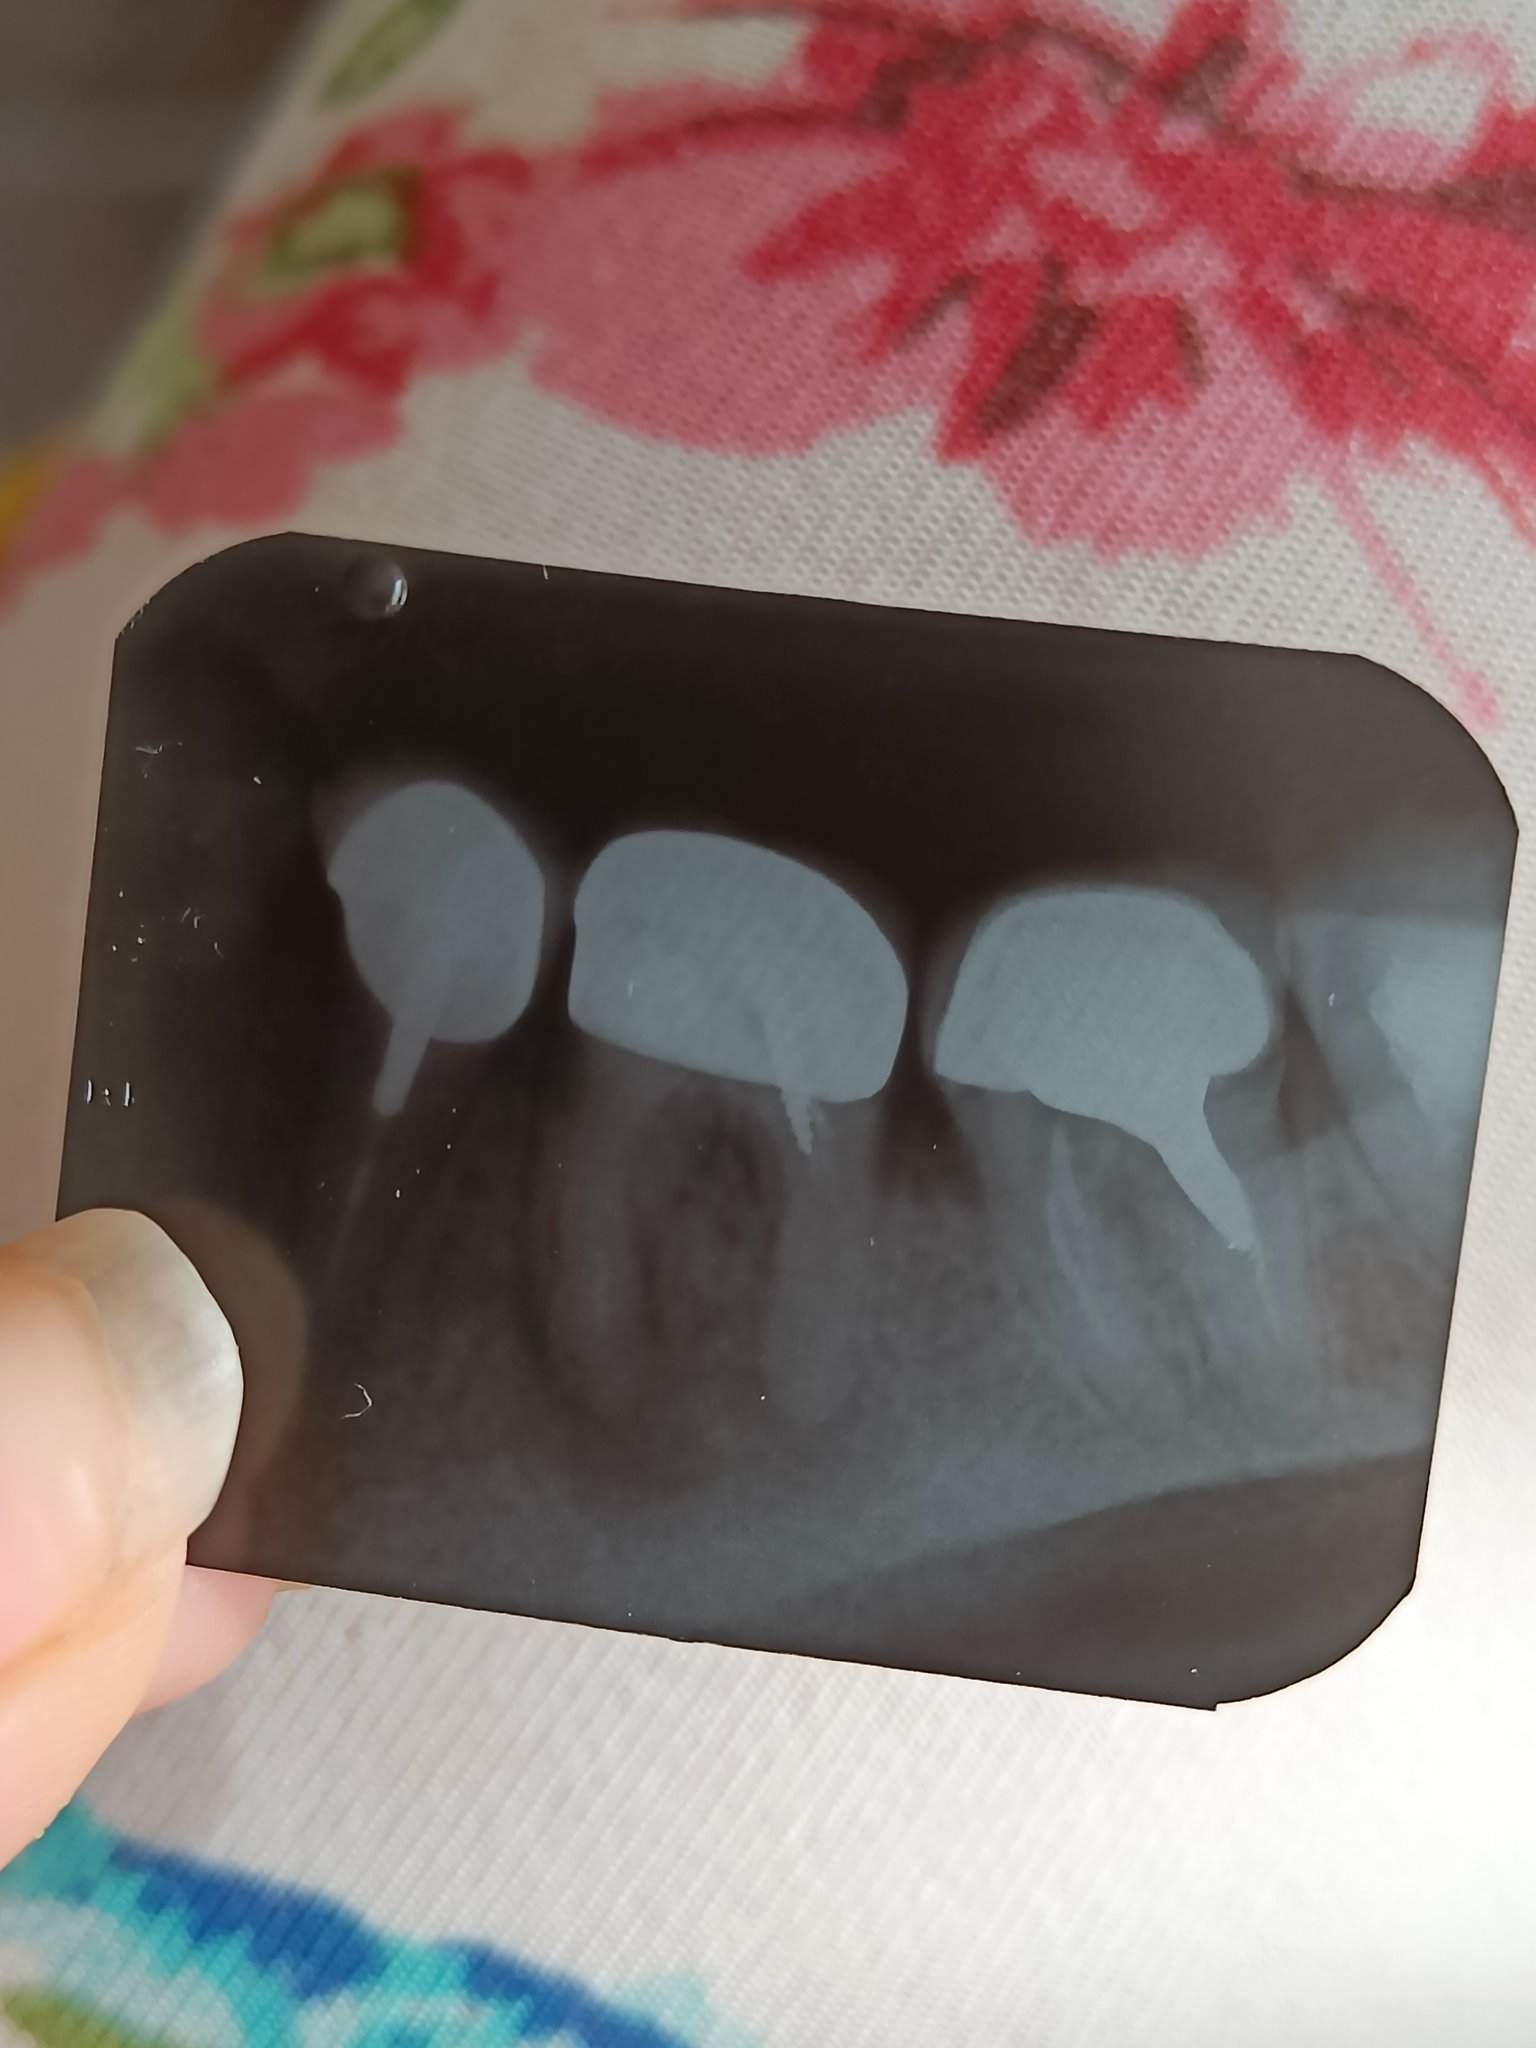

Зъбните импланти са най-добрият съвременен метод за заместване на един или повече липсващи зъби. Лечението със зъбни импланти е най-краткият и ефективен път към възстановяването на дъвкателна функция и естетика при загуба на зъби, както при по-възрастни, така и при млади пациенти.

Този метод на лечение е организиран в рамките на до 5 работни дни и е едно от най-търсените решения в клиника Дентатайм при пациенти с липса на няколко съседни зъби или тотално обеззъбяване. Също така се прилага и при пациенти, страдащи от тежка форма на пародонтит (подвижни зъби, необратими възпалителни процеси в костта и венците). Пациентът получава неподвижни конструкции (мостове) най-често в рамките на 3 дни от операцията и поради тази причина системата е известна също и като бързи (имедиатни, експресни) зъбни импланти.

Зъбни импланти, които са подходящи за пациенти с напреднала пародонтоза (пародонтит), диабет, пушачи и такива, при които липсва достатъчно кост.